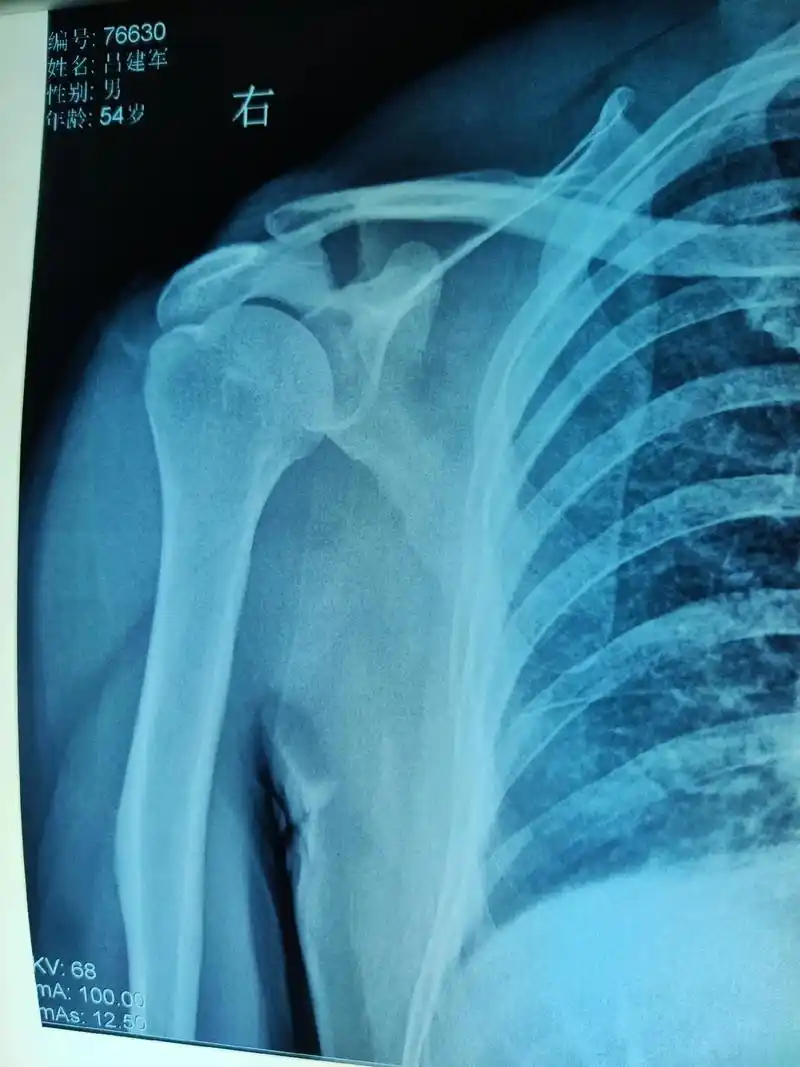

肩胛骨骨折后

肩胛骨横行骨折,锁骨粉碎骨折,肩峰骨折如何处理